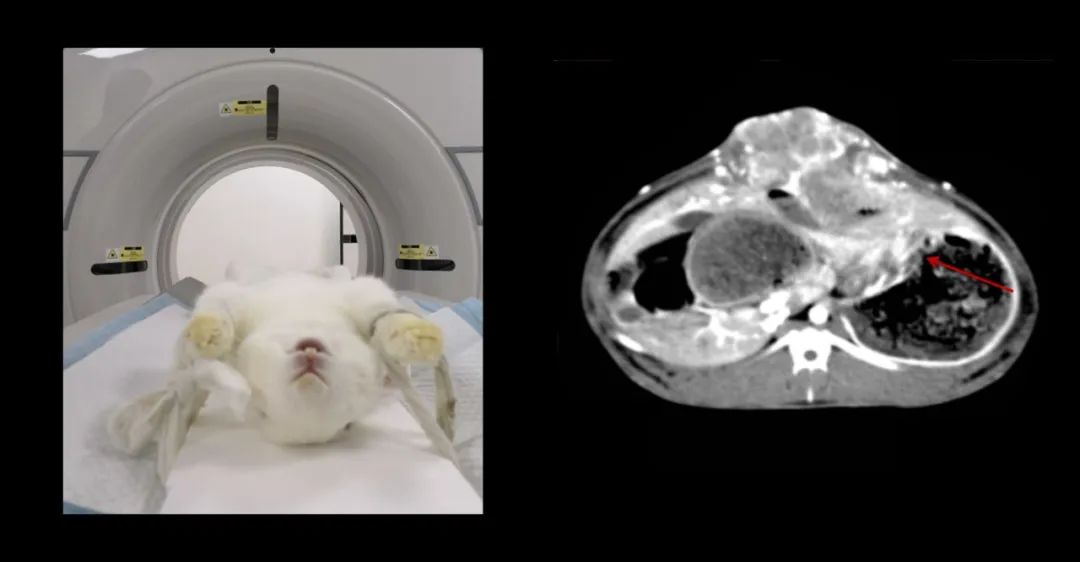

▲小白兔,白又白,兩只耳朵豎起來~這個(gè)小家伙也不幸中招,得了肝癌。